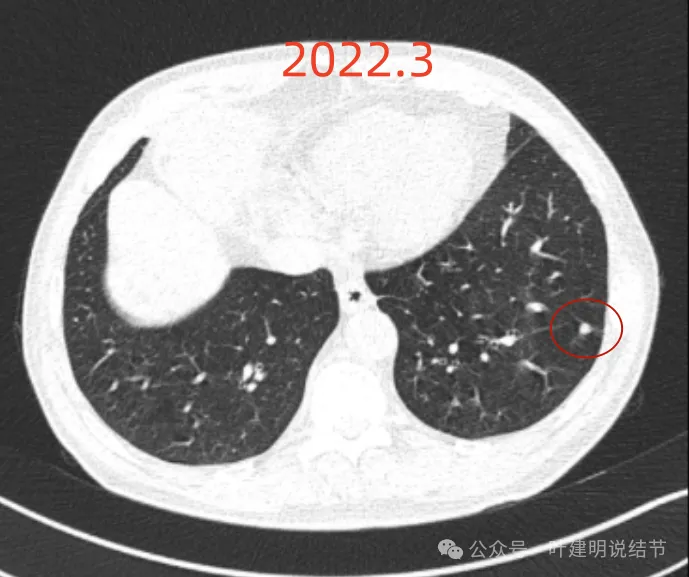

影像展示与分析:

我们先来看2022年3月主要病灶的影像:

右上叶结节实性,密度高,边缘平整,轮廓清楚,像良性些。

右下似见微小结节,实性,与边上小血管截面不太好区分,过小没什么临床意义,能随访。

左下胸膜下实性结节,轮廓稍模糊,密度较高,边缘较光,像淋巴结些,能随访。